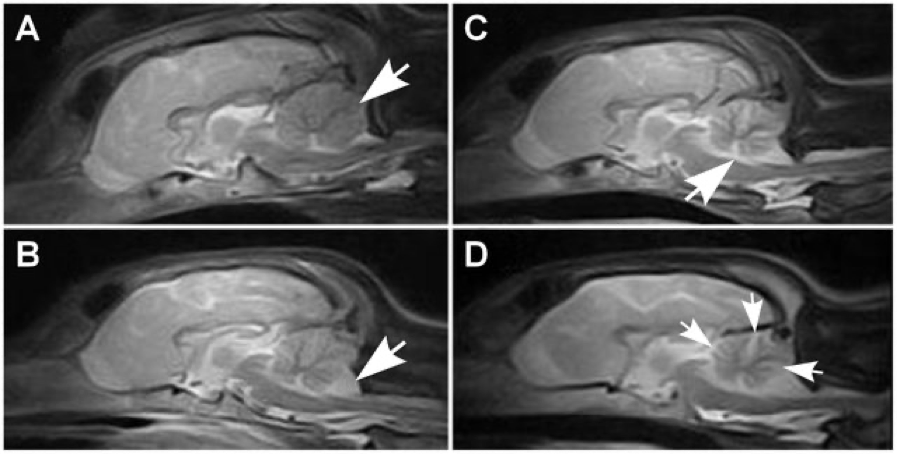

IRM CN cerv.png